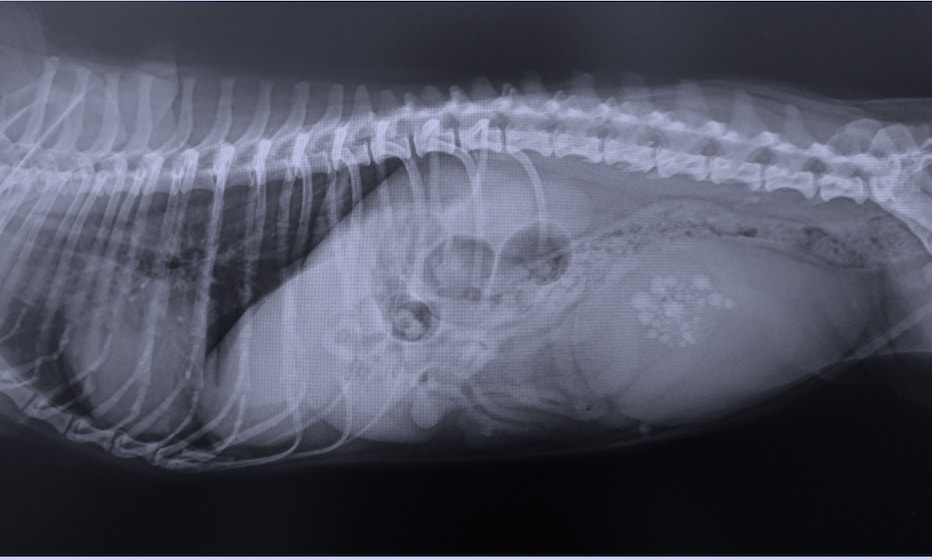

ストラバイト尿石症とは尿中のミネラル成分が結晶化し、ストラバイト結石となって膀胱や尿道にできてしまう病気です。ストラバイト尿石症の症状には頻尿や血尿、トイレの失敗などが挙げられます。排尿時に痛みが見られたり陰部を仕切りに舐めると言った症状が見られることもあります。また、結石が尿道に詰まってしまい尿道閉塞を引き起こすと、命に関わる可能性のある危険な病気でもあります。結石が作られる原因として、食事や体質のほかに、膀胱内に感染した細菌によって尿のpH(酸性度)がアルカリ性に傾くことも原因とされています。ストラバイト結石は食事療法によって溶かすことのできる結石です。ただし結石が大きすぎる場合や食事療法に反応しない場合は外科手術が適応になることがあります。ストラバイト尿石症の診断には尿検査や膀胱のエコー検査が重要になります。お家のわんちゃん、ねこちゃんに上記の様な症状が見られる時はお早めに当院にご相談ください。

犬猫共に、膀胱内に腫瘤が発生することがあり、その場合には排尿しづらそうな様子や、血尿、頻尿といった、膀胱炎などと同様の症状がよく認められます。超音波検査を行うことで、膀胱内に腫瘤が形成されているかどうかを確認することが出来ます。また、カテーテルを用いて採材を行い、細胞診検査や遺伝子検査を行うことで診断を行います。診断後、腫瘤の発生状況などにより、外科的/内科的治療を検討していきます。膀胱内腫瘤を認めた場合には悪性腫瘍であることが比較的多いこともあり、普段と異なる排尿の様子が認められた場合などは、お早めにご相談下さい。